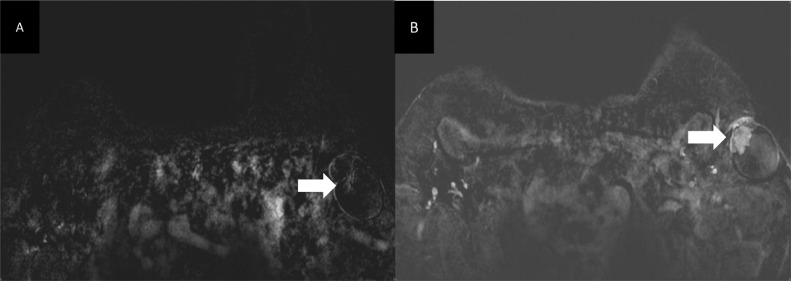

Fig. 8.

Axial T1 GE 3D subtracted sequences showing rapid homogenous enhancement of the solid component (arrow).